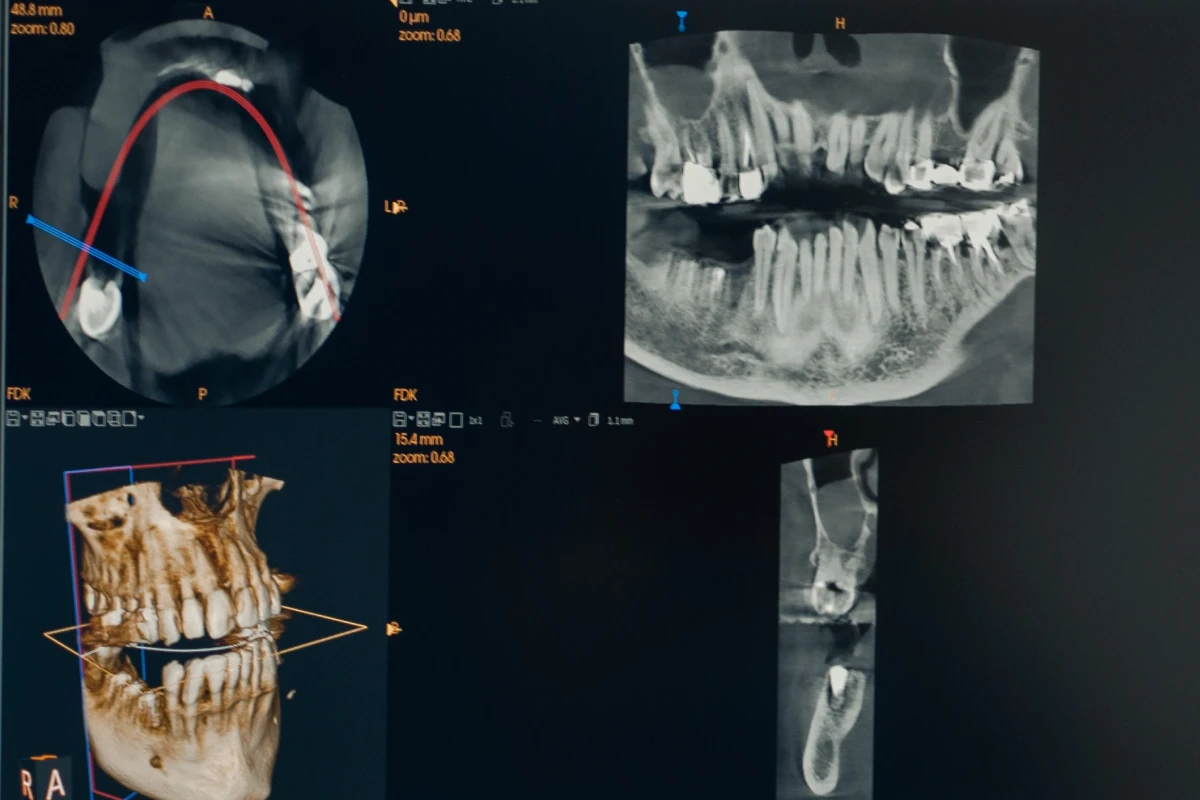

Cone Beam

Le Cone Beam est une technologie d’imagerie 3D qui permet d’obtenir une vision précise des dents, des os et des tissus environnants. Elle offre une analyse détaillée indispensable pour la pose d’implants, les bilans orthodontiques ou la détection de pathologies. Cet examen, rapide et à faible dose de rayons, améliore la précision du diagnostic et la sécurité des traitements.